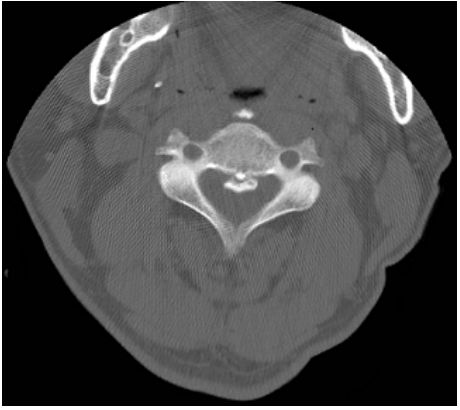

73.60 歲男性病患因長期頸部疼痛接受電腦斷層檢查,發現第 3 至第 4 頸椎有一鈣化病灶如圖。其診斷為何? (A)old vertebral fracture (B)ossification ossification of the posterior longitudinal ligament (C)ankylosing spondylitis (D)tuberculous spondylodiskitis